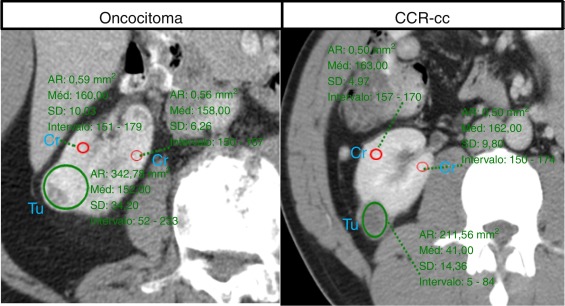

Para ambas as entidades (oncocitoma vs. CCR‐cc) desenharam‐se as áreas circulares de interesse (ROI) quer no tumor quer no córtex renal (fig. 1 ). Na fase nefrográfica determinou‐se o valor médio de atenuação de contraste em HU para cada tumor, no corte de maior diâmetro. O valor médio de atenuação do córtex renal foi determinado pelo cálculo médio entre 2 pontos diferentes com um corte de diâmetro aproximado de 0,5 cm2 . Para todos os casos, determinou‐se o diferencial de atenuação contraste entre o córtex renal e o tumor (HU do córtex ‐ HU do tumor).

Determinação da atenuação de contraste em unidades de Hounsfield no tumor (Tu) e ...

Figura 1.

Determinação da atenuação de contraste em unidades de Hounsfield no tumor (Tu) e em 2 pontos diferentes medidos no córtex renal (cr).